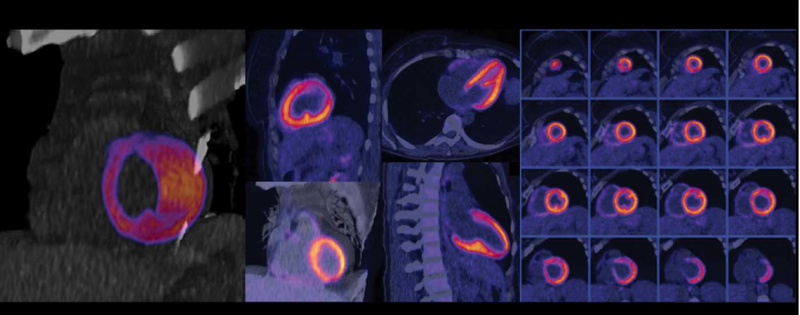

Soman also said hybrid systems that integrate a computed tomography (CT) scanner for PET-CT and SPECT-CT systems have become more popular in the market. These combined systems use CT for attenuation correct on the nuclear images, while adding CT anatomical image overlays improves the accuracy of diagnosis by visualizing the coronary anatomy to better pinpoint where blockages are causing perfusion defects.

The most recent system to gain U.S. Food and Drug Administration (FDA) clearance was the Siemens Biograph Vision PET/CT in June, which features the company's new Optiso Ultra Dynamic Range (UDR) detector technology. It is based on silicon photomultipliers (SiPMs) rather than PMTs. The detector uses lutetium orthosilicate (LSO) crystal elements, which enable faster imaging and higher light output than commonly used bismuth germanate oxide (BGO) crystals. The LSO technology also offers higher image resolution, better image quality and enabling time-of-flight (TOF) acquisition. The size of LSO crystal elements, from 4 x 4 mm to 3.2 x 3.2 mm, results in higher spatial resolution and enables a smaller footprint for the system. With the smaller crystals and covering 100 percent of the area of the scintillator array with SiPMs, Siemens said the system can deliver the industry's fastest TOF, with a temporal resolution of 249 picoseconds. The Biograph Vision also has a large 78 cm bore to help reduce patient anxiety in tight spaces and fit larger bariatric patients.

In October 2016, GE Healthcare gained FDA clearance for its Discovery MI digital PET-CT system. It uses new detector technology that allows significantly better resolution. The LightBurst Digital Detector delivers up to two times improvement in volumetric resolution. GE also said it has the highest National Electrical Manufacturers Association (NEMA) sensitivity of any time-of-flight PET system. These expanded capabilities enable up to a 50 percent reduction in tracer usage without impacting image quality.

“One of the most striking features of Discovery MI is the improved sensitivity,” said Ronny Ralf Buechel, M.D., a cardiologist and nuclear medicine physician from Zurich. “We didn’t know how low we could go with the injected activity and radiation dose, so we began to cautiously lower the dose. Now, we are around 50 percent of the injected dose for PET scans compared to the prior system — around 1 mSv for a complete rest/stress study, and what remains important for cardiac imagers is the reduced activity of ammonia without any deterioration in image quality.”